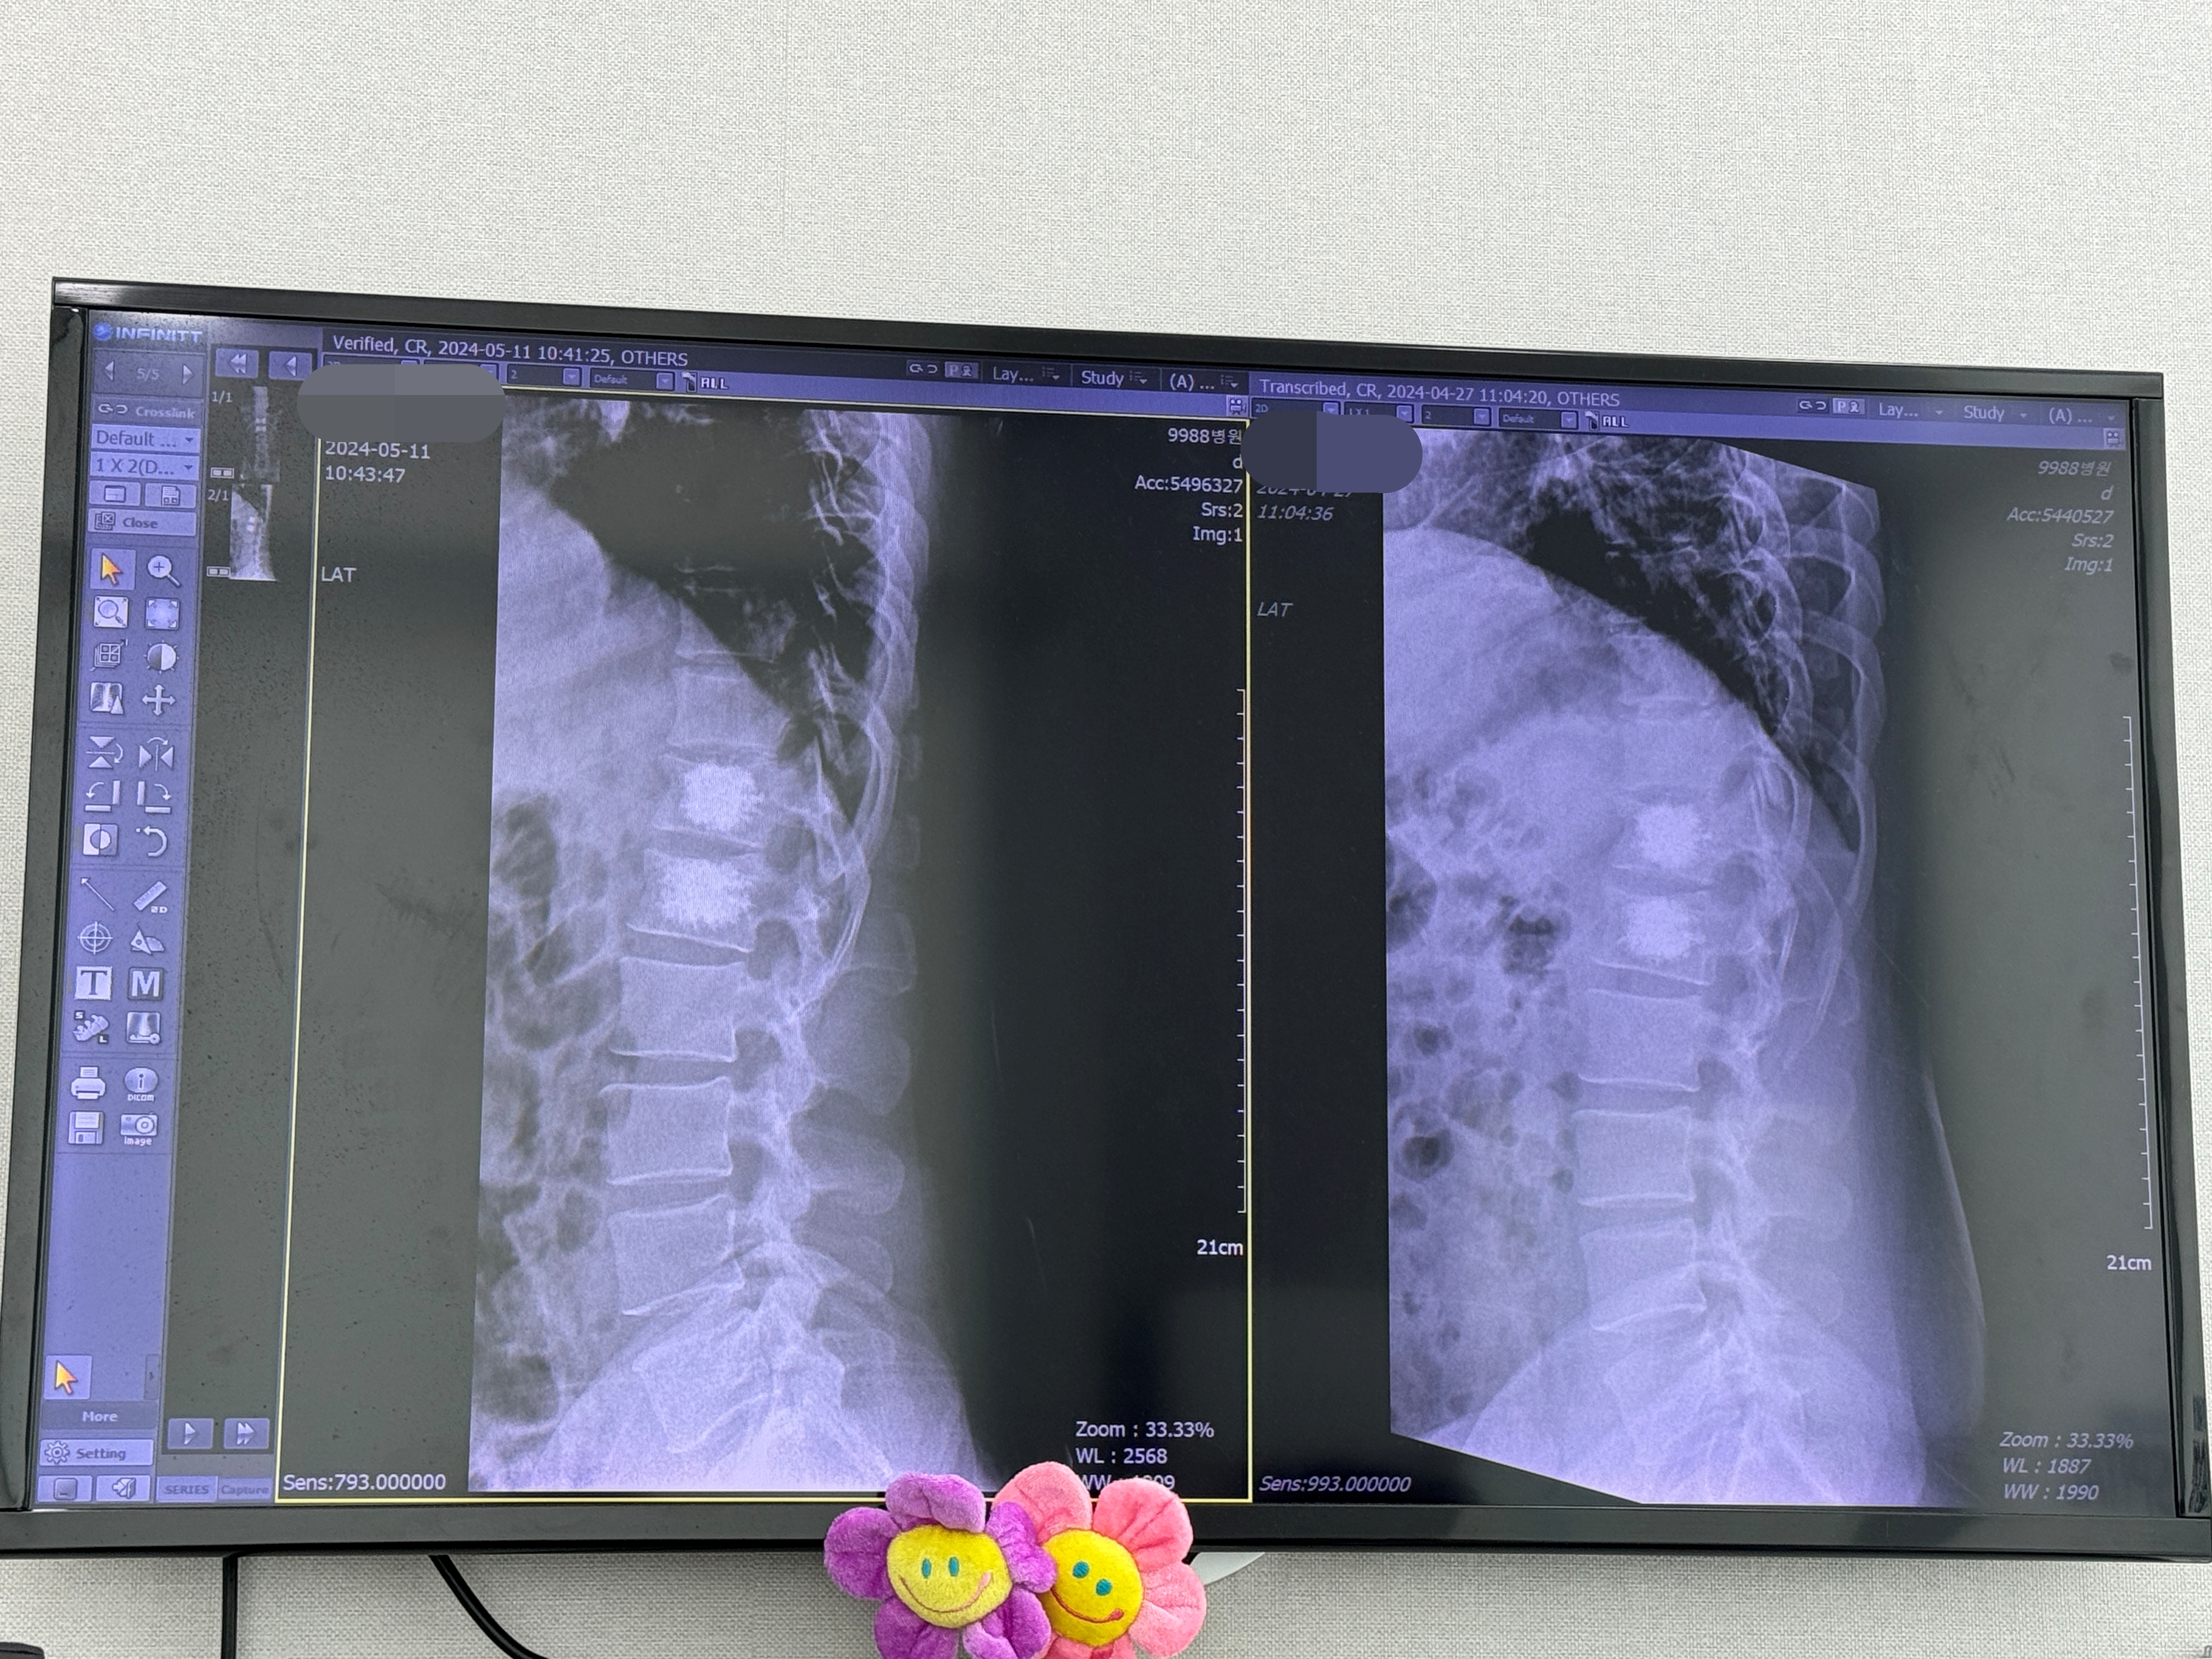

종전 내원처럼 먼저 X-RAY 사진을 촬영하고 의사 선생님을 보고 약을 타오는 과정을 거칩니다.

먼저 X-RAY를 촬영하고 진료실 앞에서 대기합니다.

처음 보는 방사선사가 있었는데 초보인지 딱 두 방 찍으면 될 일을 자세를 잘못 잡게 하여 엑스레이 사진을 여러 번 찍었네요. 대기하다 아는 아저씨를 뵈어 어떻게 병원에 왔는지 이야기를 하다 보니 제 이름을 부르네요. 진료실에 들어갑니다.

2주 전과 크게 달라지지는 않았습니다.